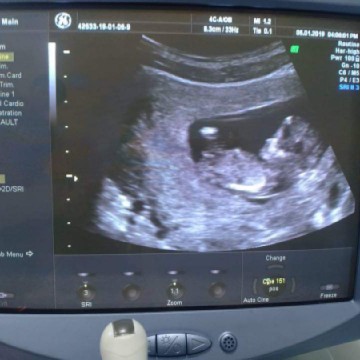

12 week ka